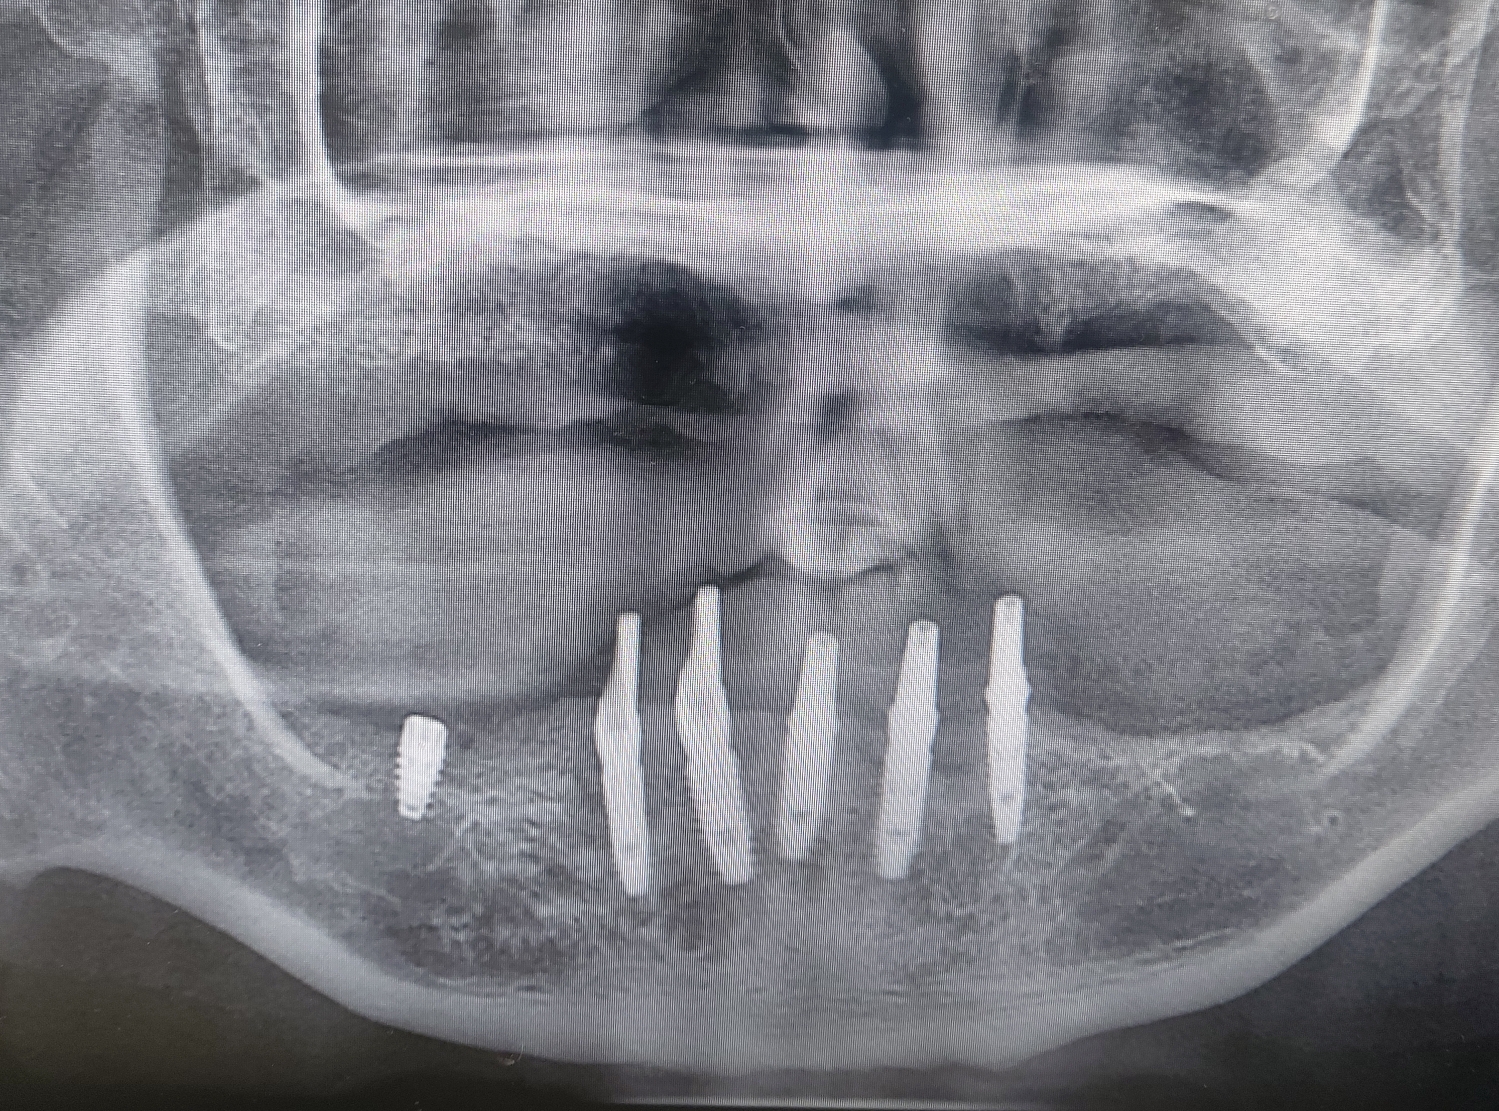

♧ 하악은 아래 임플란트 제거후 즉시 부하

이렇게 계획을 잡고 진행했습니다.

제가 초진부터 금일 완성까지 약 13개월 정도가 소요되었습니다.